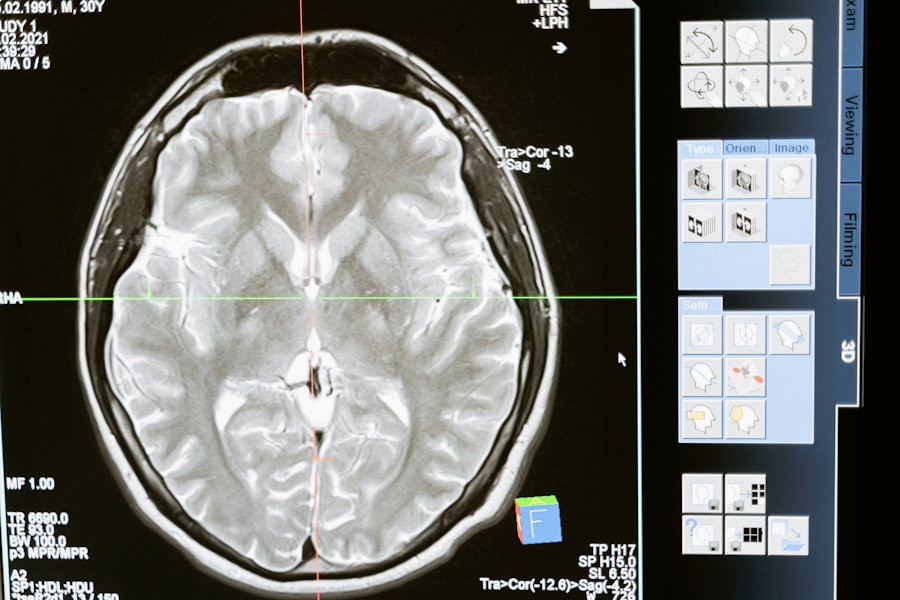

Российские ученые разработали уникальную платформу для борьбы с одной из самых опасных опухолей мозга — глиомой. Этот проект, направленный на улучшение диагностики и лечения, разрабатывается под руководством профессора Галины Павловой в НМИЦ нейрохирургии имени академика Н.Н. Бурденко Минздрава РФ.

Согласно изданию "Известия", платформа включает четыре ключевых направления: улучшение методов лечения, создание новых радиофармпрепаратов для диагностики, разработку препаратов для повышения эффективности лучевой терапии и применение таргетной терапии, которая позволяет доставлять лекарство напрямую в опухоль.

Главной особенностью этой платформы является использование аптамеров — молекул, которые способны распознавать опухолевые клетки и не затрагивать здоровые ткани, что значительно уменьшает побочные эффекты. Внедрение этих технологий в клиническую практику может стать революционным шагом в лечении глиомы и других видов рака мозга.